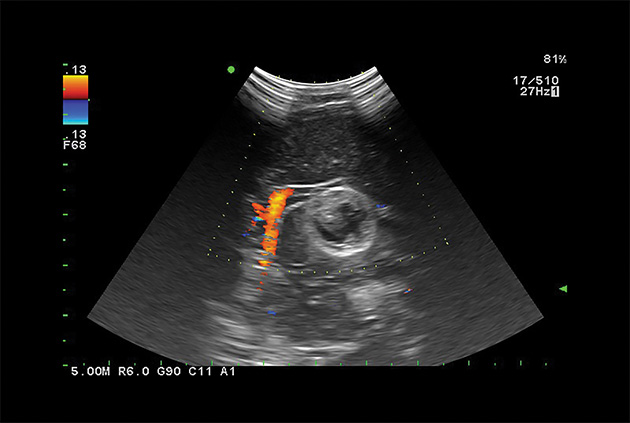

Giving the surgeon complete control

The Fujifilm Healthcare transducer utilizes the full benefits of the Wrist Articulation™ of the robotic instruments to capture real-time ultrasound imaging even at complex angles and difficult-to-reach areas.

The next level in Robotic Ultrasound

Full wrist articulation with optimized functional length.

A critical function of robotic ultrasound guidance is tumor margin identification. Fujifilm's family of robotic probes all have the optimum location of the attaching mechanism that allows for full wrist articulation of the probe. The result is an increased confidence that the tumor margins have been completely identified.